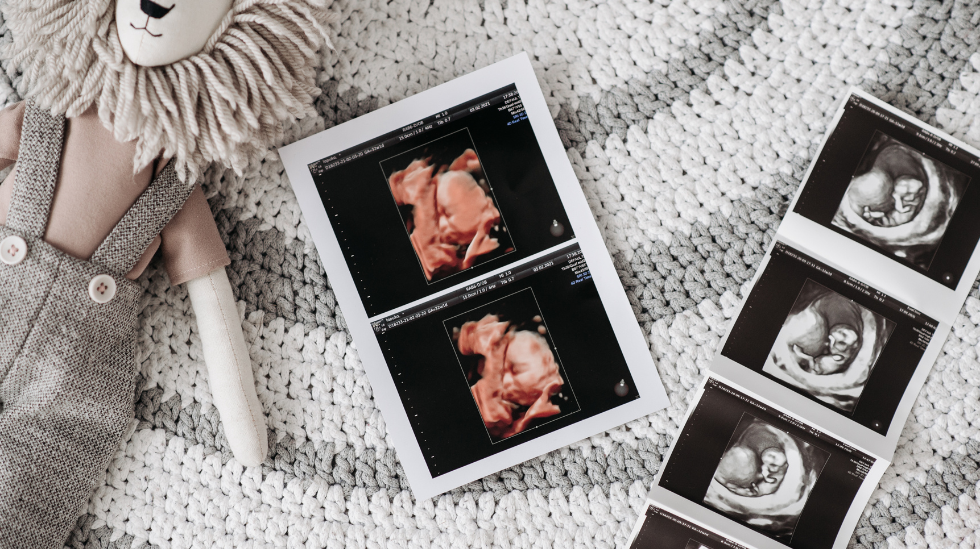

Your First Trimester

The early weeks of pregnancy are full of excitement and change as your baby begins to grow and your body adjusts. At The Elliot, we’re here to guide you from choosing your OB to learning what questions to ask and understanding the care we provide.